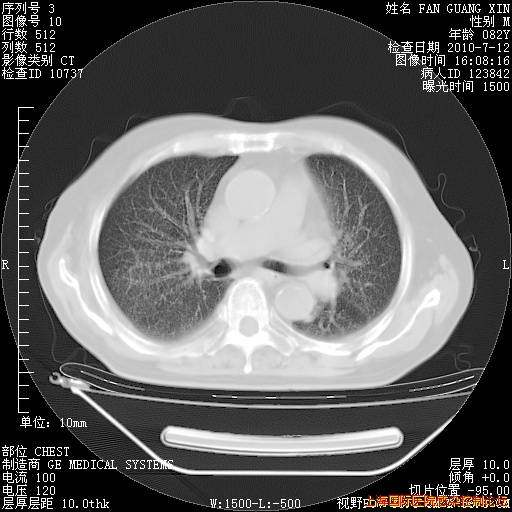

今天复查CT

今天CT

整整相隔30天的肺部CT好像有所好转啊。甲强龙减量第3天,需要观察体温。